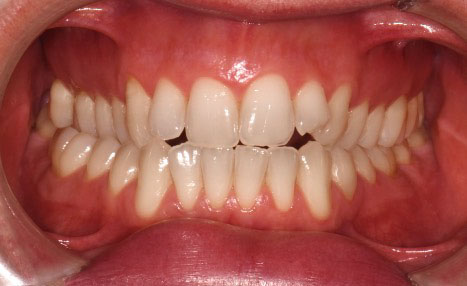

A 38-year-old male patient sought orthodontic treatment with both functional and esthetic concerns. His main complaints included the appearance of an inverted smile arc, reduced incisor display, and a general lack of harmony in his smile.

The extraoral examination revealed a long facial type with an increased lower facial third, nasolabial folds accentuated by insufficient midface support, and broad buccal corridors due to maxillary compression. Intraoral analysis showed a posterior crossbite, negative torque on posterior teeth, and an altered occlusal balance. Radiographic and cephalometric evaluation confirmed the clinical findings, with an increased mandibularplane angle and mandibular posterior rotation. This rotation contributed to a convexity of +4 mm, although the underlying problem was a retruded maxilla with insufficient midface support. Vertical facial height was also increased. Importantly, the temporomandibular joint evaluation showed a posterior condylar position with intact cortical bone, no pain, and no joint sounds.

(Images: Intraoral Initial)